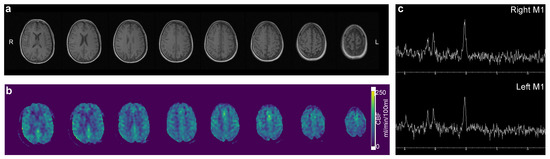

Figure 2.

Routine magnetic resonance imaging with T1 weighted (a), arterial spin labeling perfusion imaging (b), and spectroscopy (c) revealed no apparent pathology.